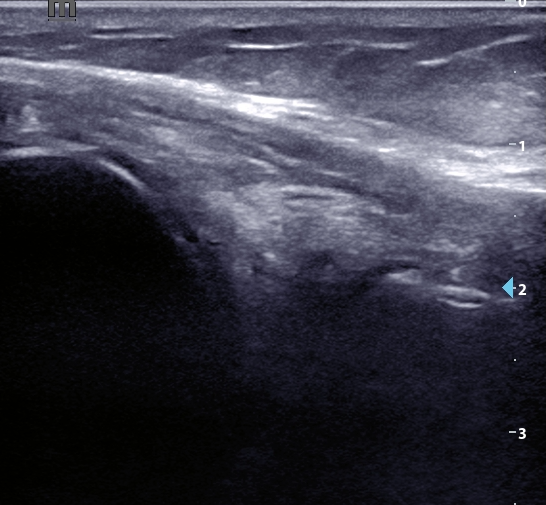

En la ecografía se observan signos de extrusión meniscal y degeneración intrasustancia del menisco externo, así como un quiste de Baker sin signos de rotura. Se observa derrame articular a nivel de receso suprapatelar. No alteraciones relevantes en otras estructuras. Se descarta TVP mediante compresión simplificada.

Meniscopatía con extrusión meniscal y Quiste de Baker asociado.

Ha sido valorado por COT, quien solicita RMN donde se objetiva rotura radial completa de menisco externo, con ligera elongación de LCA y presencia de quiste de Baker. Ha sido admitido en la lista de espera quirúrgica.

La exploración física en la gonalgia no siempre permite identificar el origen del dolor. La ecografía es un buen complemento e identifica lesiones que se pasan que en ocasiones podrían pasar desapercibidas. Además descarta signos de alarma o complicaciones, como una TVP o una rotura del quiste de Baker.